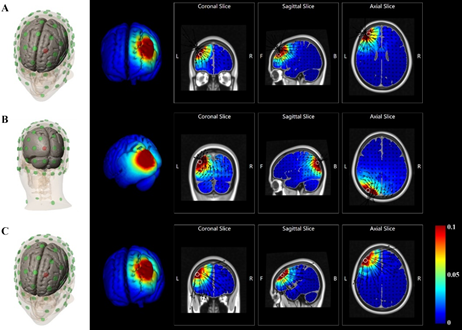

图1:四个实验刺激的电流密度图,采用Soterix HD-Explore绘制。第一行显示实验1-2对L DLPFC的阴极刺激;第二行显示实验3对左侧视觉皮层的阴极刺激;最后一行显示实验4对L DLPFC的阳极刺激。